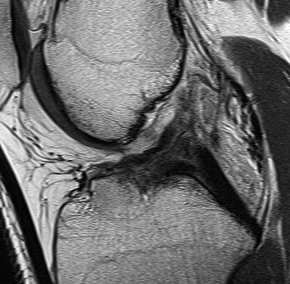

MRI

Accuracy

Smith et al Am J Roentgenology 2016

- meta-analysis of 3T MRI accuracy in diagnosing ACL tears in comparison to arthroscopy

- 92% sensitive and 99% specific for ACL tears

https://www.ajronline.org/doi/10.2214/AJR.15.15795

Normal ACL on MRI

Characteristics

- straight structure

- able to see continuity of fibres from tibial to femur

- parallel to intercondylar notch

- no anterior subluxation of the tibia

- normal to have some increased signal due to adipose and synovial tissue

Torn ACL on MRI

Findings

- high signal intensity / oedema in ACL, especially acutely

- unable to identify continuous fibres from tibia to femur

- loss of taut, straight line of fibres

Sagittal TI MRI with no femoral attachment

Sagittal T2 MRI with midsubstance ACL tear Sagittal T1 MRI with midsubtance ACL tear

Sagittal MRI with complete ACL rupture

Axial MRI demonstrating no ACL attachment to lateral femoral condyle